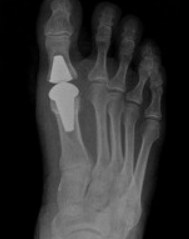

♦ 관절 고정 및 인공 관절술: 퇴행성 관절염이 동반된 경우 관절을 고정하거나 인공 관절로 치환할 수 있습니다.